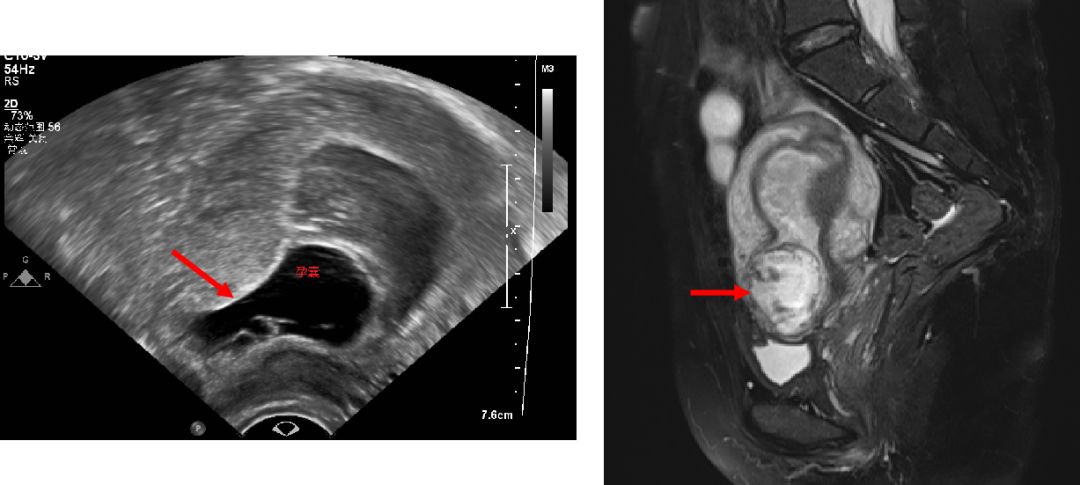

超声常用作一线筛查手段,典型图像为:

(1)宫腔内、子宫颈管内空虚,未见妊娠囊,子宫内膜清晰可见;

(2)妊娠囊着床于子宫前壁下段剖宫产切口部位肌层,部分妊娠囊内可见胎芽或胎心搏动;

(3)子宫前壁肌层连续性中断,妊娠囊与膀胱之间的子宫肌层明显变薄,甚至消失;

(4)彩色多普勒血流显像(color Doppler flow imaging,CDFI)显示妊娠囊周边高速低阻血流信号。

当超声检查无法明确妊娠囊与子宫及其周围器官的关系时,可进行MRI检查。但因MRI费用较昂贵,且检查时间相对较长,所以不作为首选的检查方法。

根据妊娠囊着床部位、妊娠囊形状、妊娠囊与膀胱间子宫肌层厚度、瘢痕处血流信号(CDFI)将CSP分为3型。医生根据分型结合患者生育意愿个体化给予治疗。